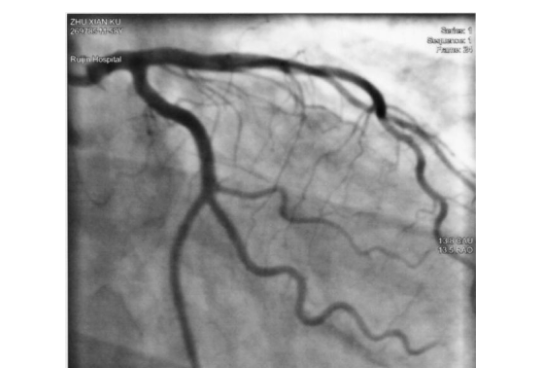

在產品上設計了明顯的顯影標記,以便在透視下觀察導管的位置和移動情況。這些顯影標記清晰可見,幫助醫生準確定位導管避免了操作中的偏差和錯誤。透視下的顯影清晰度提高了手術的安全性和準確性,同時減少了手術時間和并發癥的風險。